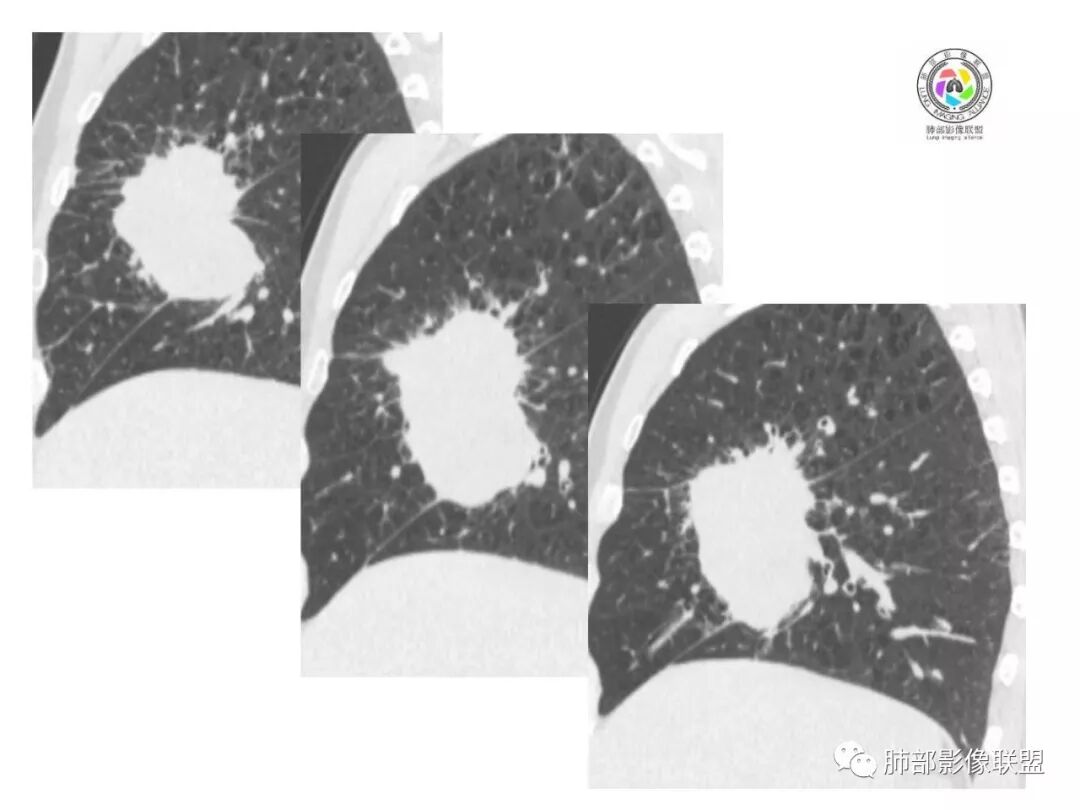

右肺巨大肿块,跨叶生长,其内见大片状坏死,坏死边界不清,血管进入,边缘受侵,病灶边缘可见毛刺及分叶,病灶强化方式速升速降,纵隔内见坏死强化淋巴结,周围肺叶小叶间隔结节样增厚,考虑恶性腺癌并淋巴结转移及癌性淋巴管炎,鉴别肉瘤。

右肺中叶可见类圆形软组织密度肿块影,右肺中叶外侧段支气管狭窄截断。肿块密度不均,边缘毛燥不规则,可见毛刺。远侧肺内可见网格条索影。增强后可见不均匀强化。纵隔淋巴结肿大,部分融合。考虑右肺恶性病变,鳞癌>腺癌,并纵隔淋巴结转移。

右肺巨大肿块,横跨上中下三叶,主体在中叶,外侧段近端支气管截断,膨隆分叶,毛刺,网格,淋巴结大,不均匀强化,湖泊样坏死,考虑恶性,低分化鳞癌>腺

右肺肿块,横跨上中下三叶,主体在中叶,外侧段近端支气管截断,膨隆分叶,毛刺,网格,淋巴结大,不均匀强化,有坏死,鳞癌?

右肺跨上叶与中叶一实性肿块影,中叶外侧段支气管堵塞,肿块有明显分叶、毛刺、棘突样改变,胸膜牵拉,周围有小花小草;增强可见病灶明显强化,病灶内可见大片状低密度区,以外侧为主,隆突下可见肿大淋巴结,恶性,考虑鳞癌可能。

老年男性,体检发现右肺巨大肿块,右肺跨叶生长,可见支气管截断,边缘见分叶,毛刺,右肺支气管不通,增强后边缘强化,内部示大片低密度坏死区,边界不清,周围肺组织小叶间隔增厚,纵隔见多发肿大淋巴结。考虑为恶性并淋巴结转移。

右肺中叶巨大肿块,外侧段近端支气管截断,横跨上中下三叶,主体在中叶,膨隆分叶,毛刺,网格,淋巴结大,不均匀强化,伴阻塞性肺炎及肺不张,湖泊样坏死,考虑恶性,鳞癌可能性较大

右肺上叶肿块,跨叶生长,分叶,支气管截断,周围支气管受压推移,内有大片坏死,周围小叶间隔增厚,纵隔淋巴结肿大,明显强化,考虑肉瘤样癌。鉴别腺鳞癌。

病灶主体位于右肺中叶,跨上、下叶,分叶毛刺,外侧段支气管堵塞,大片坏死,边界不清,内见血管进入,增强快进快出,纵隔淋巴结肿大,小叶间隔增厚,恶性,腺癌或肉瘤样癌可能。